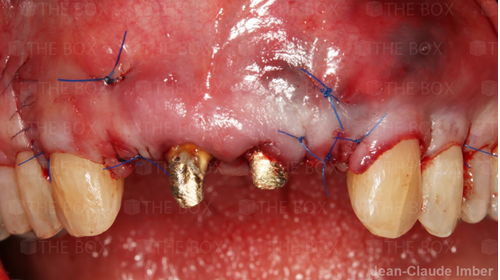

A new case was made public by Jean-Claude Imber check it out here.